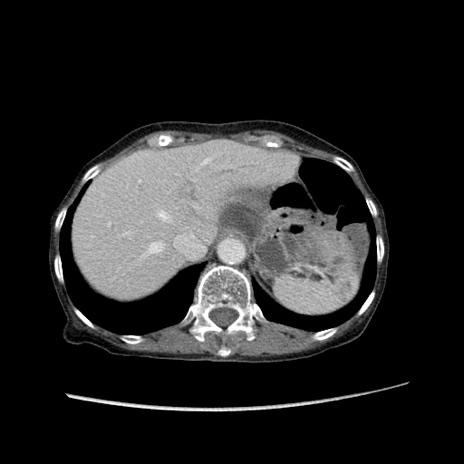

症例25(横断像)

【症例】80歳代女性

【主訴】胸のつかえ感

【現病歴】約9時間前に食後から胸のつかえた感じあり、嘔吐あり、来院。

【既往歴】胃癌(全摘)、胆摘、虫垂炎

【身体所見】心窩部に圧痛あり、反跳痛なし。

【データ】WBC 5700、CRP 0.05